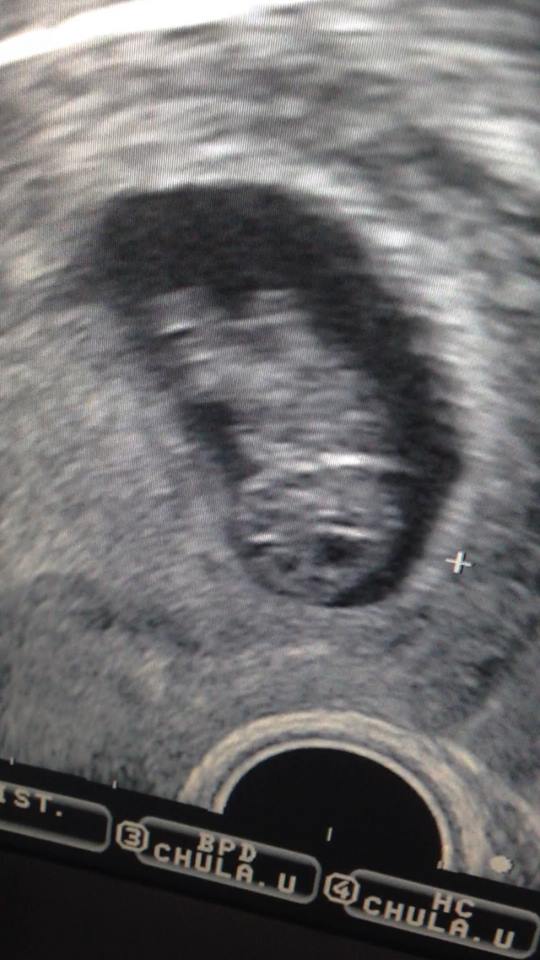

น้องแอฟหรือน้องกานต์น้อยยังไม่รู้ รู้แต่ว่าถ้าคุณพ่อนับว่าอีก 208 วันนี่คลอด 31 ธ.ค. 57 เลยนะคะได้ของขวัญปีใหม่เลย

ว่าแล้วว่าคุณพ่อต้องเห่อแน่ ขอแสดงความยินดีด้วยค่ะขอให้ทั้งคุณแม่คุณลูกแข็งแรงนะคะ